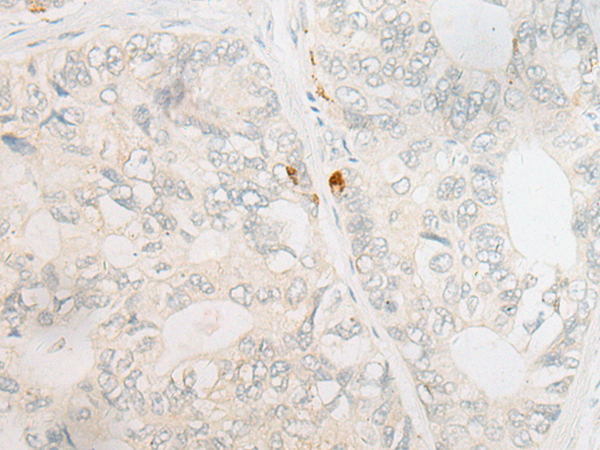

分类: 科研抗体货号: P06409别名: CTF; ECO1; EFO1; ESO1; A930014I12Rik应用: IHC反应种属: Human